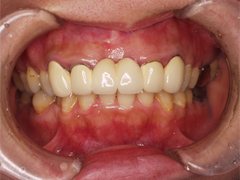

写真(1)口内写真

写真(1)

歯茎との境目に違和感がなく、ご自分のもともとの歯のように見えています。

同じような自由診療を行なっても、完成にはこのような差がでてまいります。